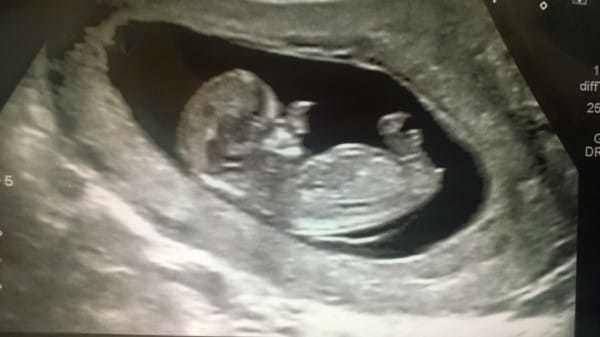

Amy Poole hamileyken şok edici bir haber aldı. Ultrasonda bebeğinin suratında bir anormallik gözüküyordu.

- haftada Amy’nin bebeğinin burnunun etrafındaki yumuşak dokunun kontrolsüz şekilde geliştiği farkedildi.Amy, oğlunun yaşıtları gibi görünmeyeceğini biliyordu. Ancak bu onu hiç üzmedi.Amy bebeğini Galler’deki bir üniversite hastanesinde dünyaya getirdi.